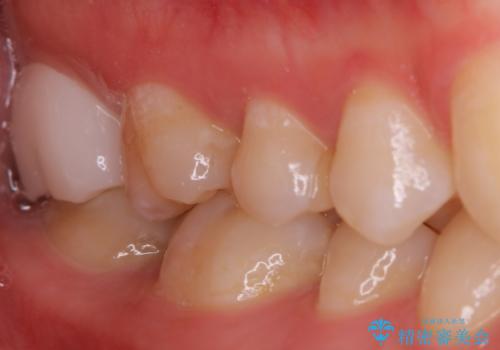

PGA(ゴールド)インレー 深い虫歯の治療